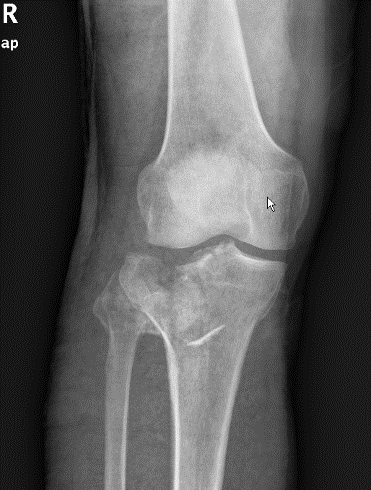

1、图1-2 术前X片见骨折似乎不是特别严重

2、图3-6 术前CT见胫骨平台严重塌陷、劈裂

胫骨平台骨折的病人,如果在30年前大多数医院应该会选择保守治疗。那时CT尚未普及,而仅凭X片会低估其损伤的严重程度,容易产生可不必手术的假象,也难以准确判断骨折移位情况。即使想做手术,也没有什么好的内固定可供选用。